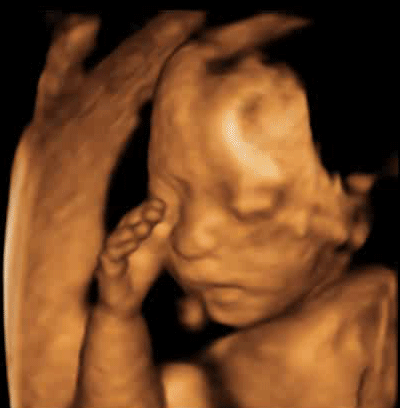

做完四维检查,她被孩子“丑”哭了

有些孕妈妈看到自己家宝贝的检查照片后,

差点被胎宝宝丑到哭泣!

以为自己怀了一个外星人

其实,这个阶段的胎儿长相几乎都差不多,

准确说都不咋好看,

看到胎宝宝的“真容”不过是检查附赠项目,

超声影像(四维彩超)检查不仅能够准确发现胎儿表面畸形,在胎儿微小病变方面也有突出表现,能够通过清晰的画面对胎儿的体表进行检查,及早发现鼻骨缺失、脊柱裂、大脑、肾、骨骼发育不良等各种畸形情况。